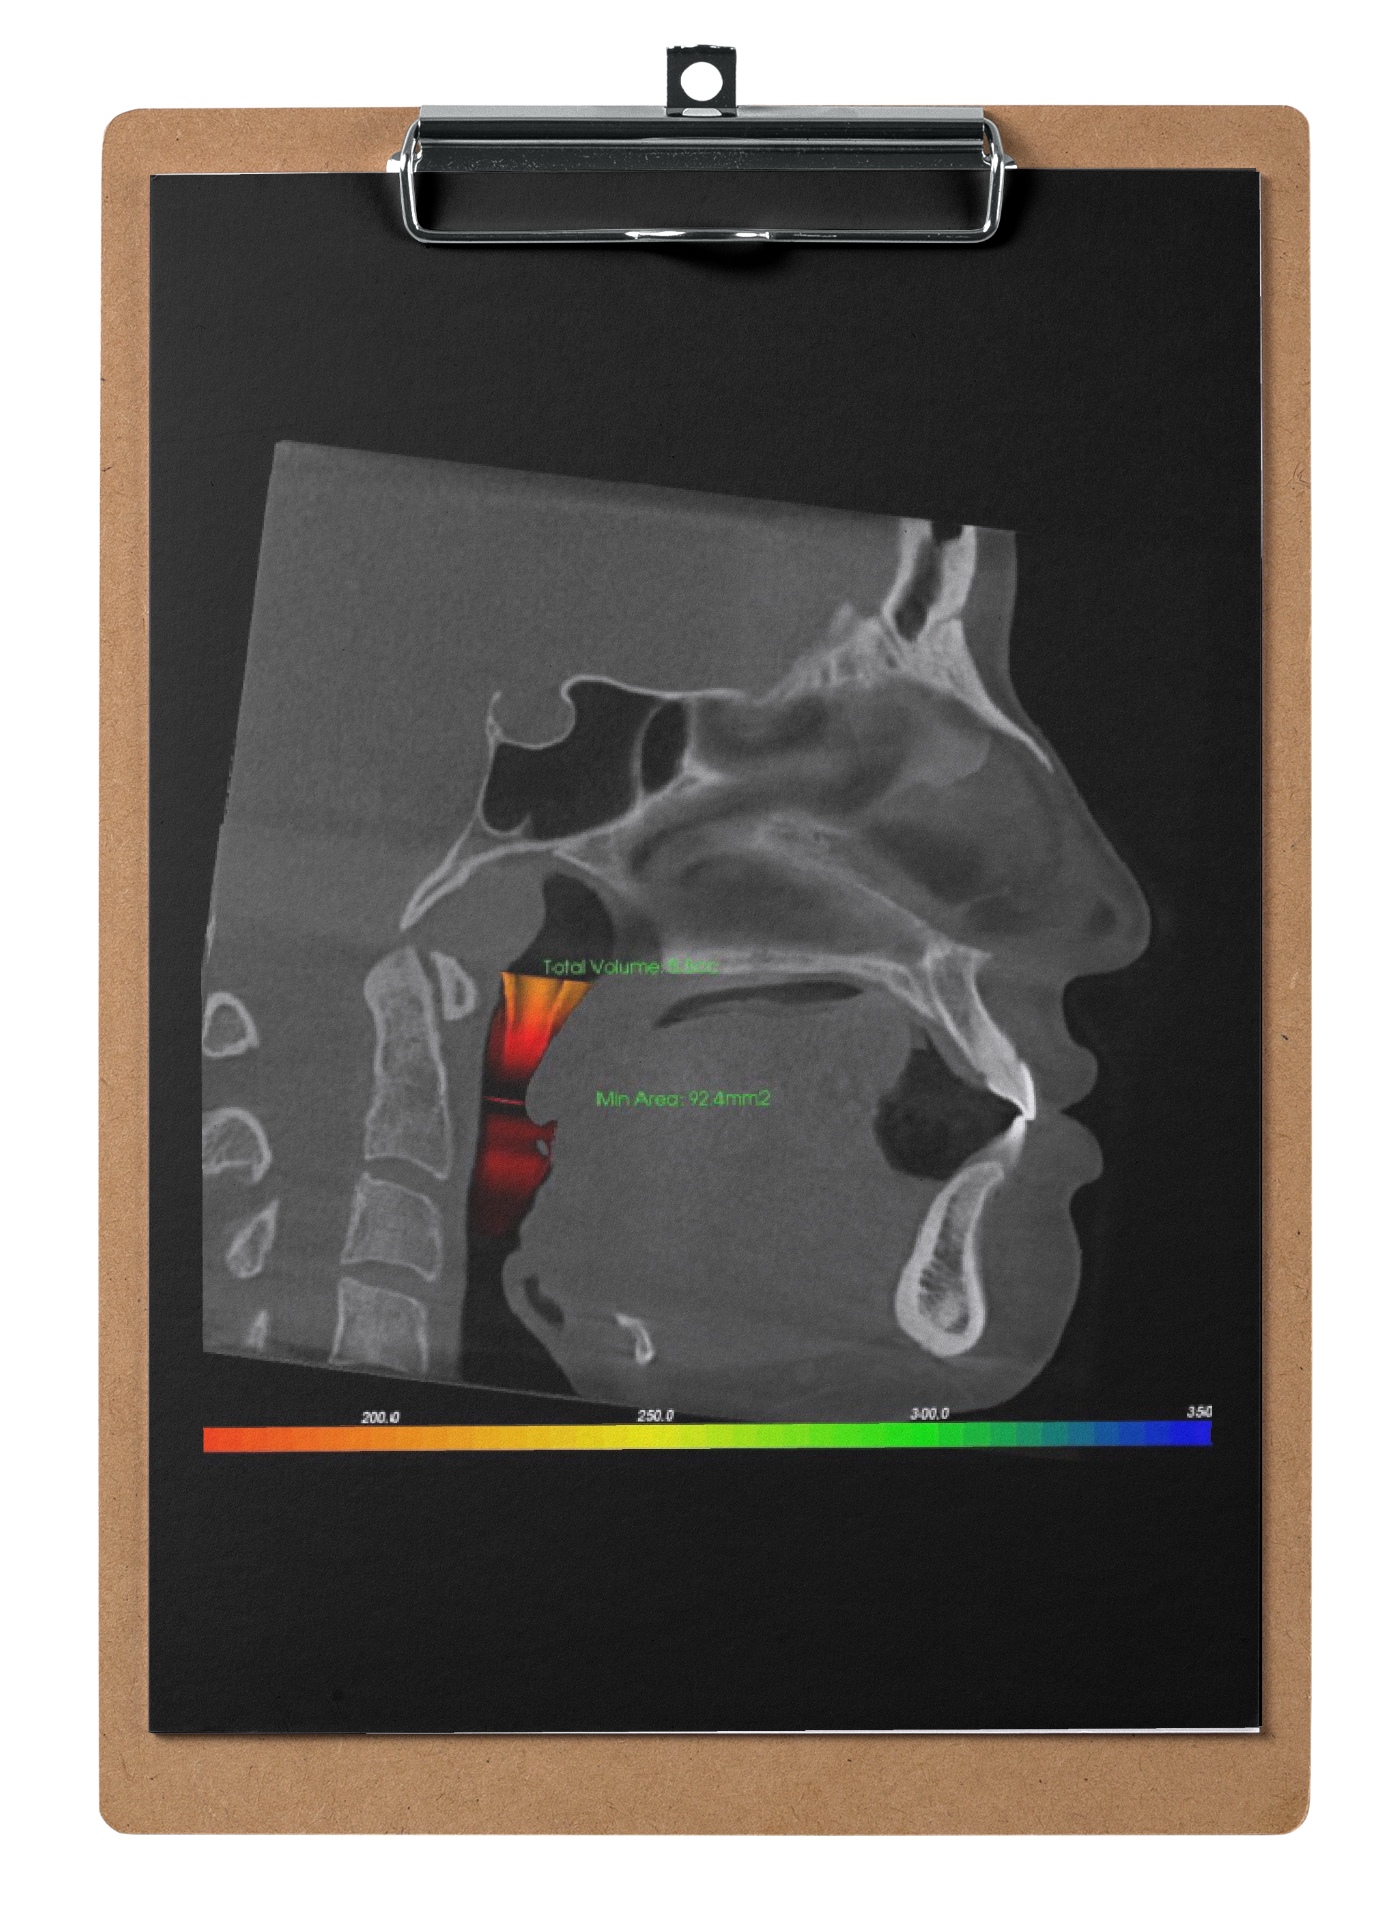

Как отсутствие работы с положением языка в детском возрасте может привести к челюстно-лицевой операции SARPE у взрослых пациентов

3. Разбор клинических кейсов

4. Визуализация результатов после проведения комплексного миофункционального подхода